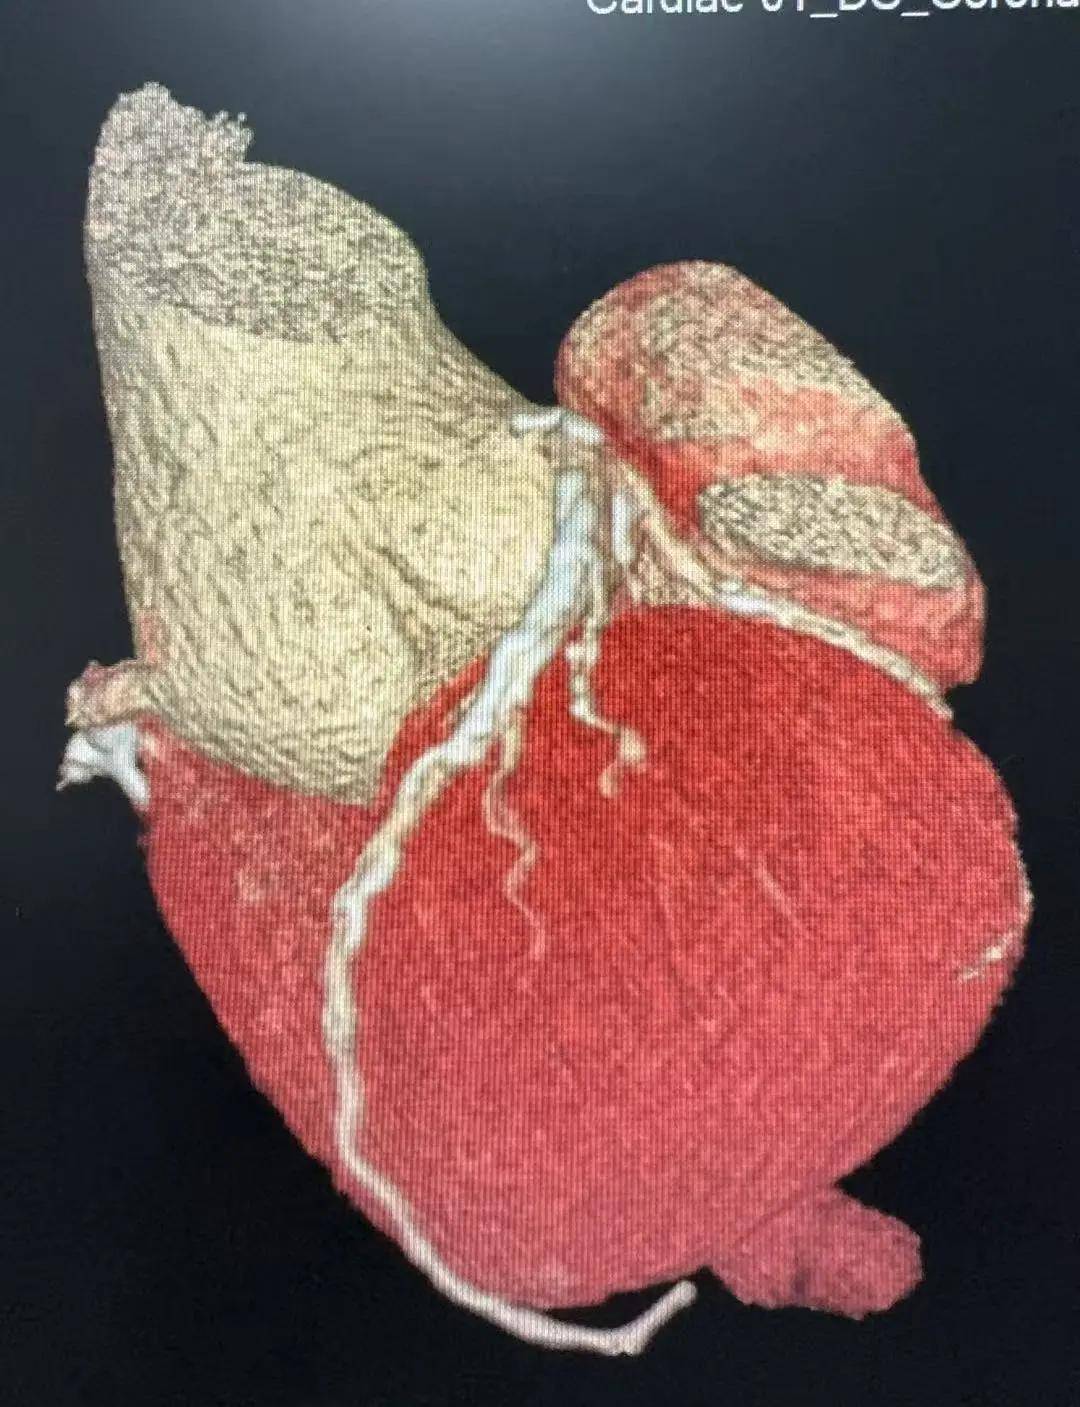

患者的冠状动脉重度狭窄,主动脉根部膨出一直径约5.7厘米的动脉瘤,主动脉瓣大量反流,一旦发生主动脉瘤破裂就会危及生命,这种情况同样需要手术治疗。

经胸外科、心血管外科、重症医学科、麻醉科多学科会诊,专家团共同为患者制定出一套"先行右全肺切除、择期心血管外科手术"的序贯治疗方案。

目前,患者老段已顺利出院,后续将根据病情择期接受心血管外科手术,将体内潜藏的“定时炸弹”彻底拆除。(于海峰 于炎术)